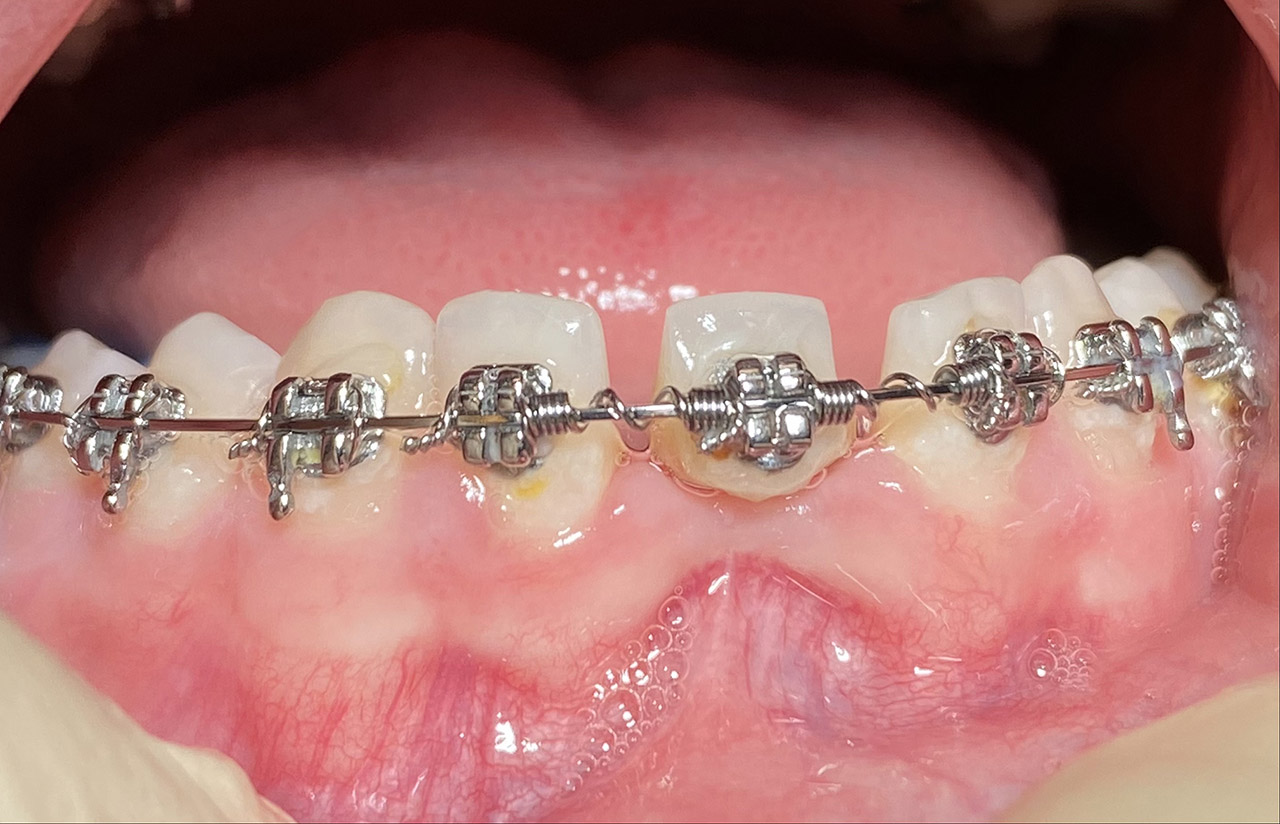

Prophylaxe/professionelle Zahnreinigung:

Zur Motivation, Information und Instruktion einfärben der Beläge (bakterieller Biofilm) bei jungem Patienten in kieferorthopädischer Behandlung. Reinigung der Zähne mit Pulverstrahltechnik minimalinvasiv und zahnschonend und wo noch nötig gezielt mit Ultraschall.

Das Resultat 45 Minuten später.